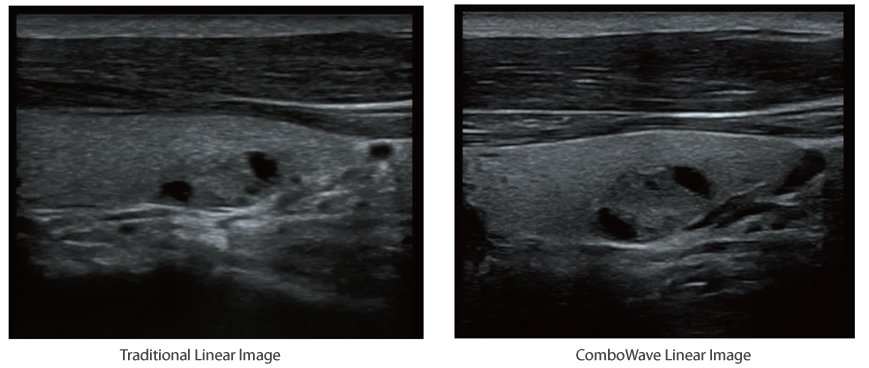

Compared with traditional transducers, ComboWave transducers utilize a new type of composite piezoelectric material to dramatically optimize the acoustic spectrum and reduce acoustic impedance. Further integrated with Instromedix India unique 3T technology, the ComboWave linear transducers allow you to experience outstanding performance with extreme image resolution and uniformity in thyroid, breast, vascular, and more.